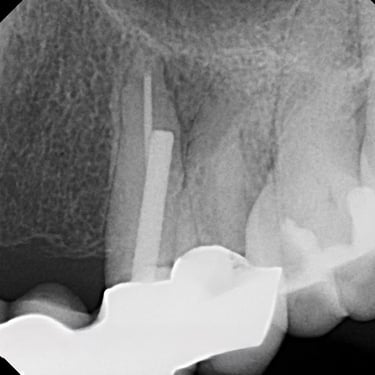

Perforación Radicular

Una perforación radicular es una abertura anormal en la raíz del diente, generalmente debido a un procedimiento dental fallido o una caries profunda.

Los pacientes pueden sentir dolor y notar hinchazón en la encía.

El tratamiento incluye la reparación de la perforación y el tratamiento de conducto. Es crucial reparar la perforación para evitar una infección.